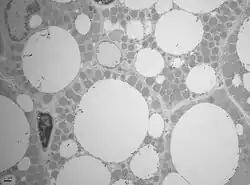

Caractéristiques histologiques

Les adipocytes bruns multiloculaires sont moins nombreux chez l'adulte que les adipocytes blancs uniloculaires. Contrairement à ces derniers qui ont un noyau repoussé à une extrémité de la cellule par la vacuole lipidique unique contenant du triacylglycérol, les adipocytes multiloculaires possèdent un noyau central.

Les vacuoles sont de taille variable. On dénote beaucoup de mitochondries ainsi qu'une riche vascularisation. La couleur brune quant à elle s'explique par la présence de fer au niveau de la matrice des mitochondries.

Le tissu adipeux brun possède une morphologie pseudoglandulaire. L'innervation est assurée par le système nerveux sympathique adrénergique.